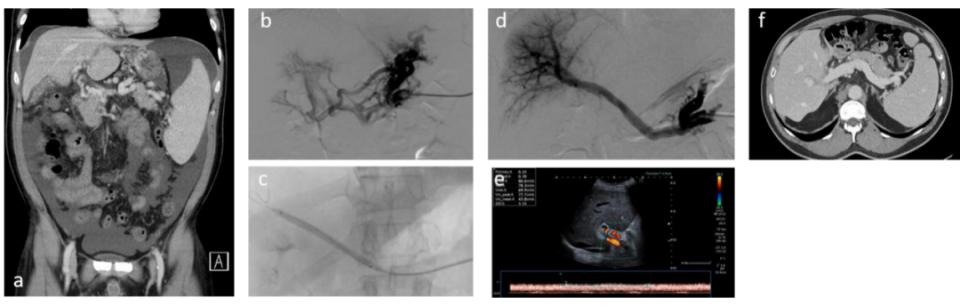

另一方面,对于肝内门静脉血流正常(即无明显肝纤维化)患者,PVR后可能无需常规联合TIPS。仅当门静脉造影证实静脉回流不足,或再通术后门静脉压力梯度持续升高,才考虑TIPS(Artru F, et al. JHEP Rep 2022;4(8):100511)(图5)。

图5. 经脾途径门静脉再通术:影像学表现及长期预后(图源自文献)

此外,Artru等发现,某些因素(如慢性腹痛和Marot 3分型)与再通术后原发性通畅率降低相关。这时将PVR与TIPS联合使用可能会优化治疗效果。